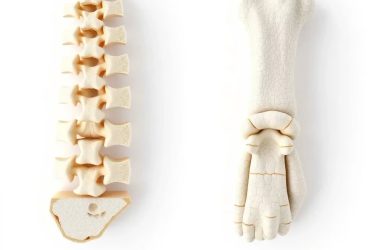

مرکز سنجش تراکم استخوان کرج اولین و باسابقه ترین مرکز تخصصی تراکم استخوان در استان البرز میباشد که با پیشرفتهترین دستگاههای سنجش تراکم استخوان تجهیز شده و مورد وثوق اکثریت جامعه پزشکی اعم از اساتید معتبر و بزرگ روماتولوژی ارتوپدی، غدد و … قرار دارد.

این مرکز به صورت تخصصی به انجام سنجش تراکم استخوان میپردازد و چون خدمات تصویربرداری دیگری ندارد تمام هم و غم خود را در راستای اعتلا و اعتباربخشی به حوزه دانسیتومتری گذاشته است